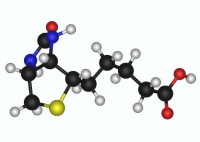

What is Biotin

Версия 1.0 от 20.10.2011

Offline info reference for Vitamin H or B7.